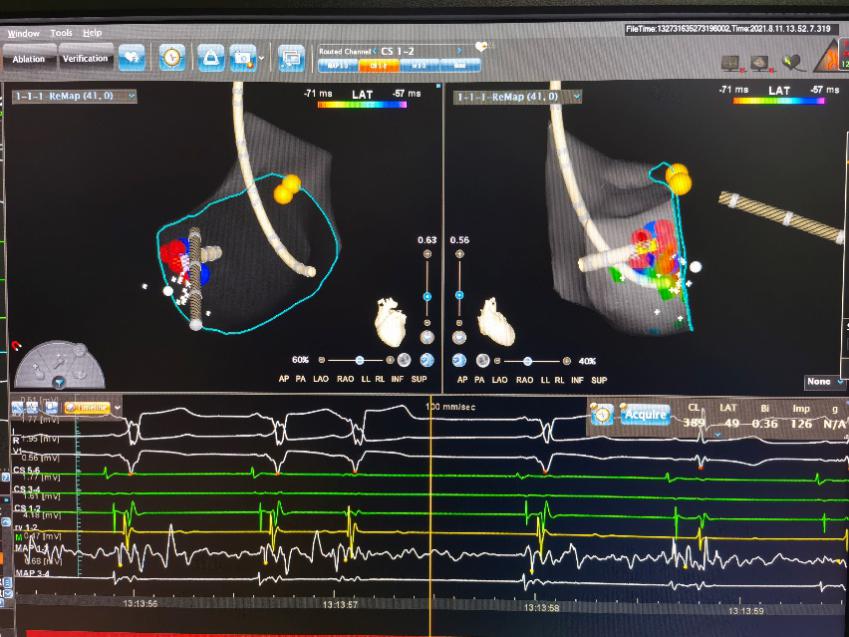

1周前恬恬再次发病,家属再次联系我院,坚决要求手术治疗。由于孩子年龄小、风险大,儿童心血管副主任医师刘丽萍、袁勇华、刘震宇和成人心内科副主任医师张良对恬恬的病情进行全面评估及讨论,制定了严密的手术方案。8月11日,医疗团队为恬恬实施手术,术中通过电生理检查确定恬恬为“房室折返性心动过速”,在三维标测下找到靶点,并成功消融,术中几乎无出血,辐射量极少。术后恬恬迅速恢复,在术后第三天就顺利出院了,家长十分感激。

刘丽萍主任介绍,阵发性室上性心动过速(paroxysmal supraventricular tachycardia, PSVT)是儿童就医的最常见心律失常之一,有研究显示儿童PSVT的发病率为1/1 000~1/250,PSVT得不到及时终止或者反复发作,可能导致心力衰竭和晕厥发生,甚至有猝死风险,部分预激综合征还可以导致预激性心肌病,严重影响儿童的日常生活、运动和学习。经导管射频消融是目前根治室上性心动过速的唯一手段。 恬恬的心电图类型属于预激综合征,这是儿童中最常见的一种室上性心动过速,药物控制只能减少发作,不能根治。据统计,该手术的成功率可达90%以上。儿童射频消融手术由于难度大,很多医疗机构未开展此项技术。恬恬是儿童心血管专科完成手术的最小年龄的患者,团队利用“绿色”三维标测技术,手术成功率明显提高,而且辐射量少,对儿童来说安全有效,且更有利于维护儿童的健康。